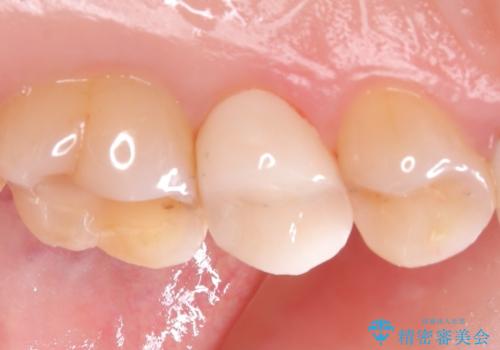

オールセラミッククラウンを選択されました。

メタルインレーを除去し、その下にあったう蝕を除去したうえで、CRにて築造を行い形成しました。印象時は圧排し、シリコンにて精密に行っています。